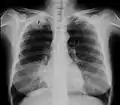

Um tumor de Pancoast é um tumor do ápice pulmonar, ou seja, um tipo de câncer de pulmão definido principalmente pela sua localização situada no topo do pulmão esquerdo ou direito. É tipicamente associado a um histórico de tabagismo.